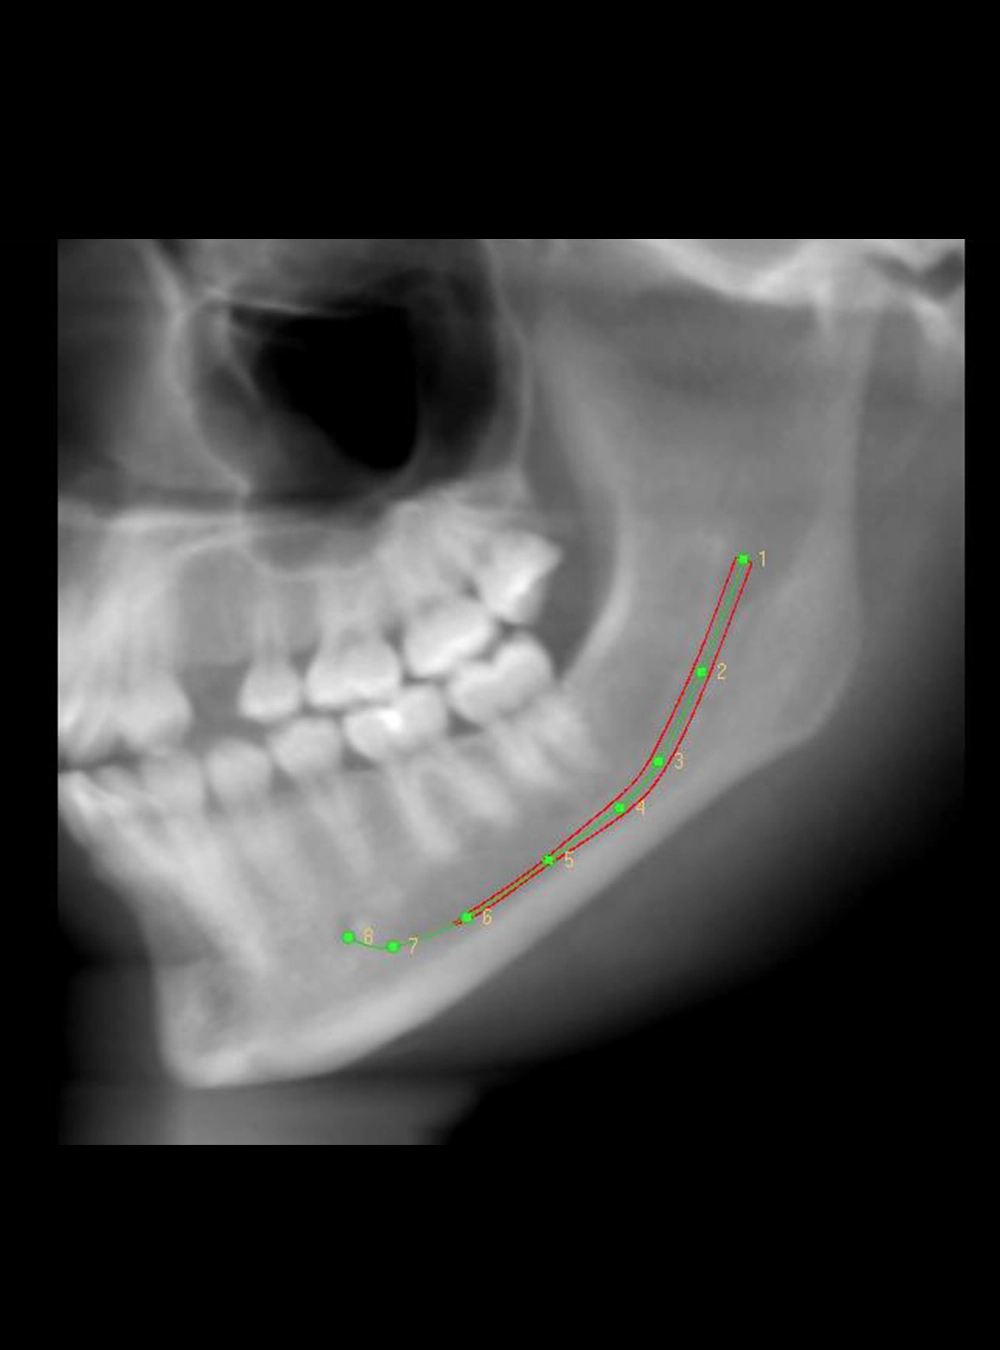

Canal Mandibular

Guías Quirúrgicas

Un elemento protésico usado en odontología por especialistas en implantología para direccionar de manera más exacta y correcta en la posición y colocación del implante.

Proceso Digital

Con software 3D de punta, especializado en modelos y proyecciones.